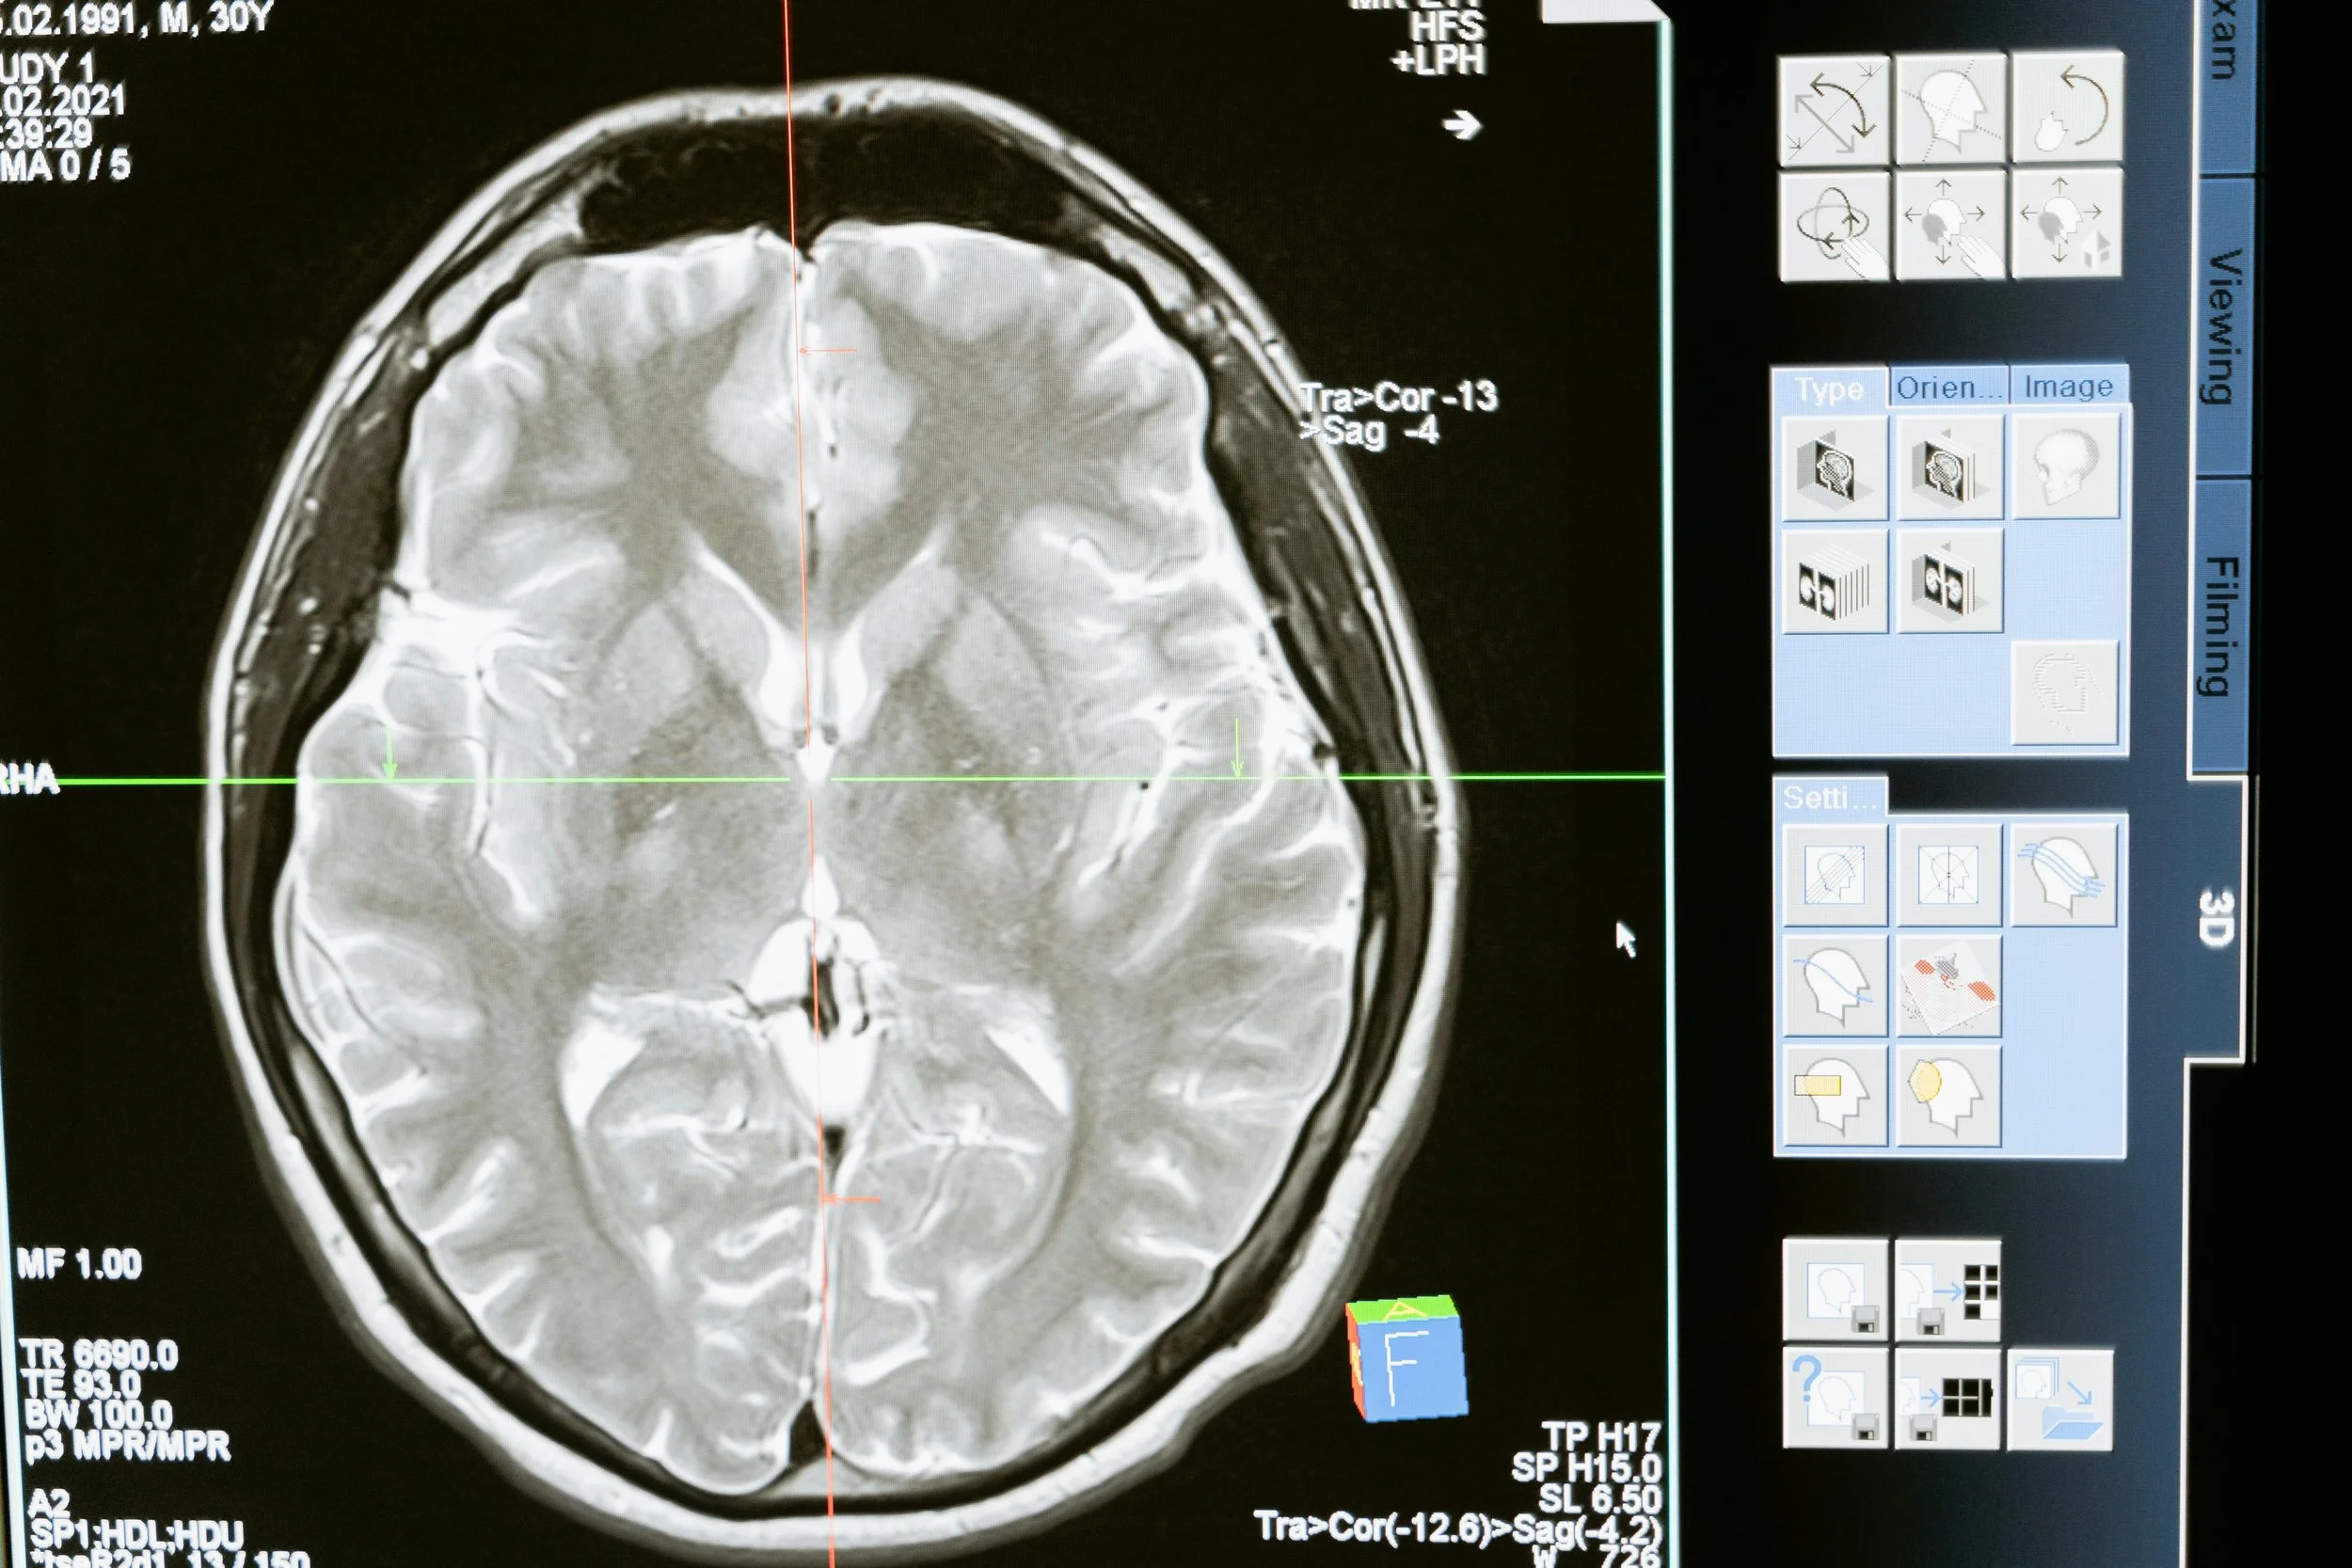

CADe (電腦輔助偵測) 系統主要功能在於透過分析醫學影像,如超音波、X 光、電腦斷層掃描 (CT) 及磁振造影 (MRI),快速標記出影像中可能存在的病變區域,協助醫師早期發現潛在異常。值得注意的是,CADe 僅提供影像標記,並不給予明確的診斷結果。例如: